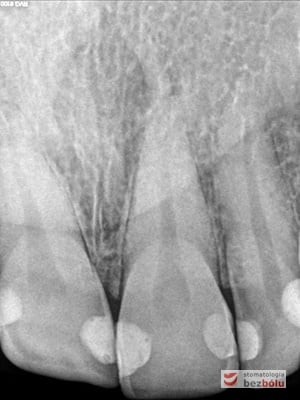

Pacjentka lat 37 zgłosiła się z silnymi dolegliwościami bólowymi siekacza centralnego na górze po stronie lewej. Ząb był w trakcie leczenia kanałowego w innej placówce. Jedno wizytowe leczenie kanałowe polegało na starannej instrumentacji kanału korzeniowego oraz wypłukaniu podchlorynem sodu, a następnie starannym odtłuszczeniu i wysuszeniu systemu korzeniowego. Kanał został szczelnie zamknięty metodą termokondensacji ciśnieniowej przy pomocy instrumentarium, tj. system B i Obtura. Kontrola radiologiczna potwierdziła szczelność wypełnienia oraz ujawniła obecność kanałów bocznych, które bez starannego wypełnienia mogłyby stać się przyczyną infekcji w obrębie wyrostka zębodołowego. Wypełnione kanały boczne przypominały dymiące fabryczne kominy. Leczenie zostało zakończone odbudowaniem zrębu koronowego z udziałem ćwieka z włókna szklanego, który został otulony materiałem kompozytowym nanohybrydowym. Jedno wizytowe sprawne leczenie endodontyczne przyniosło pacjentce natychmiastową ulgę, a odbudowa korony zredukowała ryzyko złamania zęba.